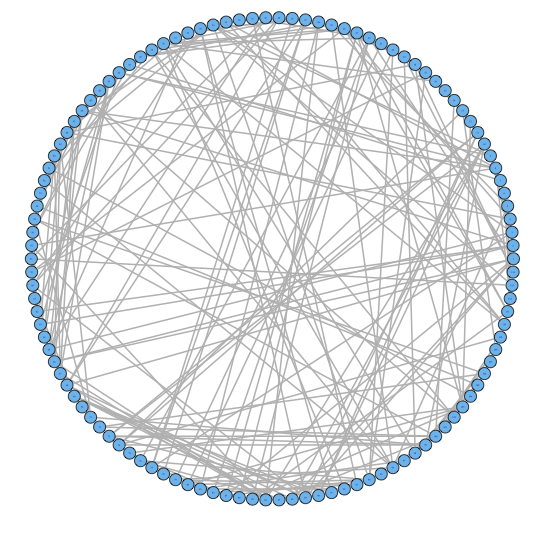

2.2 Challenge I: Two Levels of Network Variability

For our two-level problem (1.1.1), we must account for two sources of network variability when conducting population inference: (i) variability between subjects within a group and (ii) variability of the network selection procedure within a single subject. To see this, let us study a real multi-subject fMRI example. In Figure 2, we show estimated functional brain networks for subjects from the UCLA fMRI ABIDE data set INDI (2013). We describe the details of this data set, our pre-processing, and brain parcellation later in the Case Study in Section 5. In the top and middle panels, we estimate brain networks for each subject using graph selection methods for Gaussian graphical models (see Section 3.1 for details) and plot these as circle graphs to easily visualize network differences. It is clear that there are not only differences between autistic subjects and control subjects, but there is also large heterogeneity across subjects within each group. This is well-known in the neuroimaging literature (Milham et al., 2012; Nielsen et al., 2013), and makes finding statistically significant differences between subject groups much more challenging.

Less well studied in neuroimaging, is the second source of variability which arises from estimating networks for each subject instead of directly observing the networks. In the bottom panel of Figure 2, we re-estimate brain networks for a single control subject with bootstrap resampled data. It is clear that there is major intra-subject variability arising from our graph selection procedure. Indeed in neuroimaging, test–re-test studies which conduct brain imaging on the same subject in repeated sessions have shown high variability in the subject’s estimated brain networks (Wang et al., 2011). This also motivates the necessity of using a two-level model like (1.1.1) for population network inference as opposed to the one-level model and test statistics of the standard procedure.